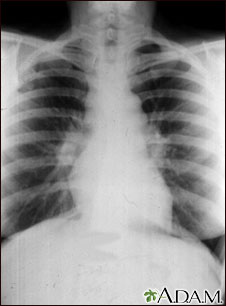

Sarcoid, stage I - chest x-ray

Sarcoid is primarily a lung (pulmonary) disease. In the early stages, a chest film may show enlargement of lymph nodes in the center of the chest near the heart (mediastinum).